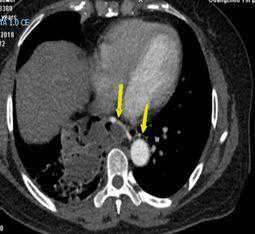

图1肿块边缘多发迂曲血管影,滋养动脉

图2纵隔窗表现

图4隔离肺组织由腹主动脉与胸主动脉共同供血

胸部CT扫描检查无痛苦、创伤小,是目前临床上常用的诊断手段。由于低分辨率平扫不能显示异常血管,难以与其他相关疾病鉴别,导致误诊率高,因此,临床上如怀疑肺隔离症,应予以行胸部增强CT+CTA,以准确发现异常滋养血管。

它可以长成这样↓↓↓

图7左下肺内侧基底段团状密度增高影,内可见不规则含气空腔及气液平